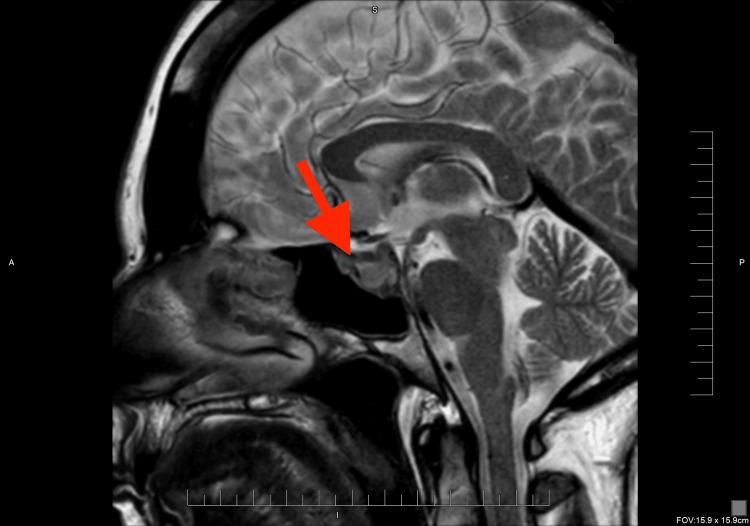

Sex hormones play a crucial role in the development and growth of meningioma. It was observed that meningiomas increase in size and become more symptomatic during pregnancy. Similarly, the use of hormonal therapy, including gonadotropin-releasing hormone (GnRH) agonist, can be associated with an increased risk for meningioma. We reported a 45-year-old woman with a past medical history of hypothyroidism and mild hyperprolactinemia who received hormonal therapy for infertility, including GnRH. She has experienced a persistent headache and left retro-orbital pain with eye movement. Her MRI brain scan revealed a soft tissue mass involving the sellar and left cavernous sinus with a slight impingement of the optic chiasm and left optic nerve, concerning for meningioma or pituitary adenoma. Further laboratory workup showed secondary adrenal insufficiency, which was treated with replacement glucocorticoid therapy. Following tumor resection and histological examination, the diagnosis of sellar meningioma was confirmed. This case report shows a rare association of fertility hormonal treatment with sellar meningioma and how it is challenging to distinguish meningioma from other sellar masses, such as pituitary adenoma, based on clinical presentation and imaging studies.

性激素在脑膜瘤的发生和发展中起着至关重要的作用。据观察,脑膜瘤在孕期体积会增大且症状会加重。同样,使用包括促性腺激素释放激素(GnRH)激动剂在内的激素疗法,可能会增加患脑膜瘤的风险。我们报告了一名45岁女性,她有甲状腺功能减退和轻度高泌乳素血症病史,因不孕症接受了包括GnRH在内的激素治疗。她一直头痛,眼球活动时伴有左眶后疼痛。她的脑部MRI扫描显示鞍区和左侧海绵窦有一软组织肿块,对视交叉和左侧视神经有轻微压迫,怀疑为脑膜瘤或垂体腺瘤。进一步的实验室检查显示继发性肾上腺功能不全,并接受了糖皮质激素替代治疗。肿瘤切除及组织学检查后,确诊为鞍区脑膜瘤。本病例报告显示了生育激素治疗与鞍区脑膜瘤之间罕见的关联,以及基于临床表现和影像学研究将脑膜瘤与其他鞍区肿块(如垂体腺瘤)区分开来具有挑战性。